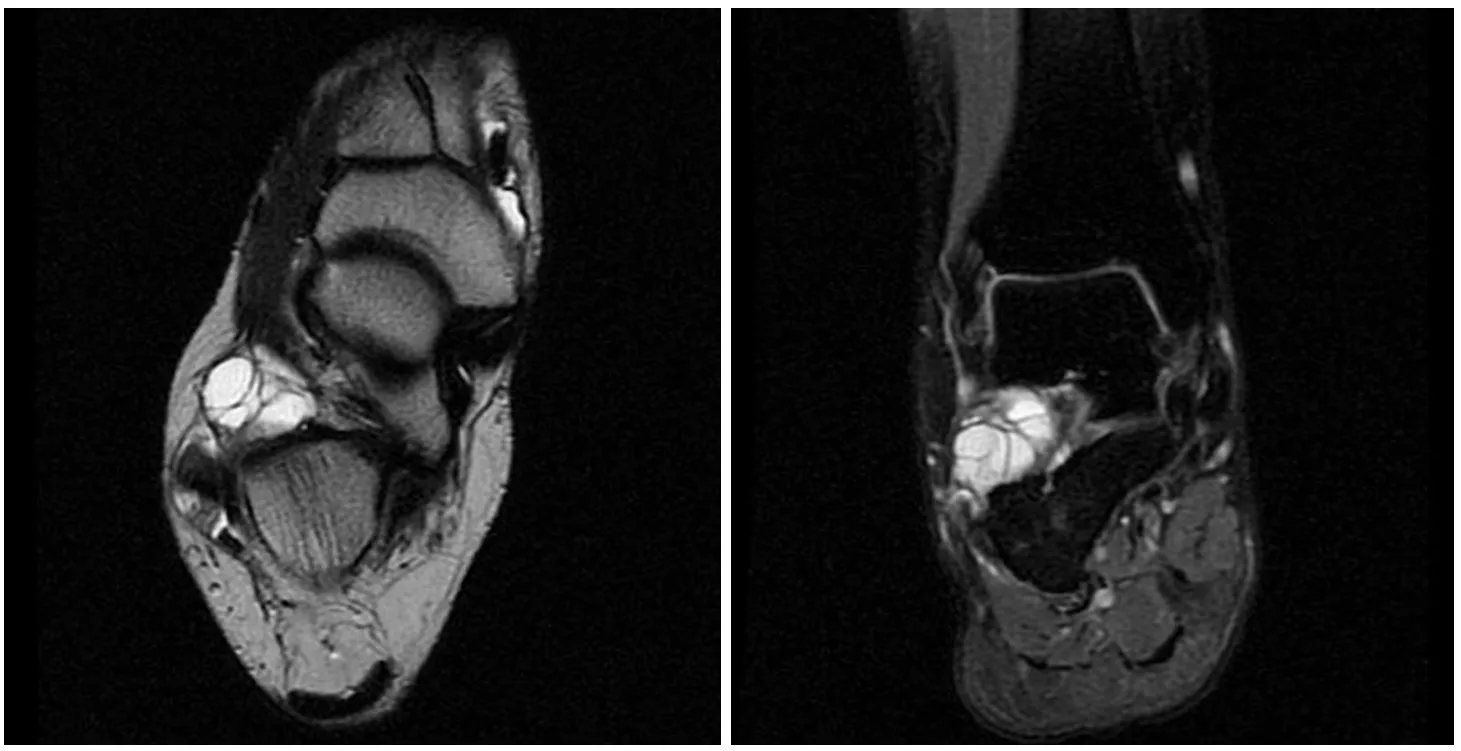

Фото и диагностика кисты Бейкера